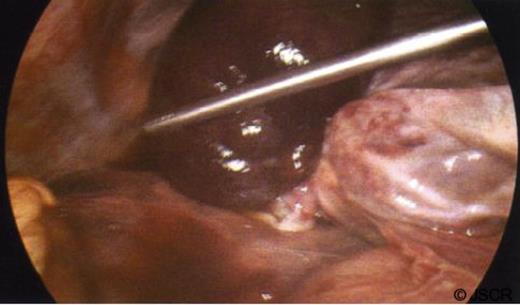

A diagnosis of acute acalculous cholecystitis was made, and the patient was referred for a cholecystectomy. At laparoscopy, he was found to have a gangrenous torted gallbladder (Figures 2 and 3), with a 360 degrees clockwise torsion. The gallbladder was detorted laparoscopically and an attempt was made at laparoscopic dissection, but Calot’s triangle was too inflamed and suffused with blood to clearly identify the anatomy and so the procedure was converted to open. The gallbladder was safely resected, and a cholangiogram revealed normal biliary anatomy with no bile duct stones.

Laparoscopic view of the gangrenous gallbladder, with a 360 degrees clockwise torsion on its mesentery